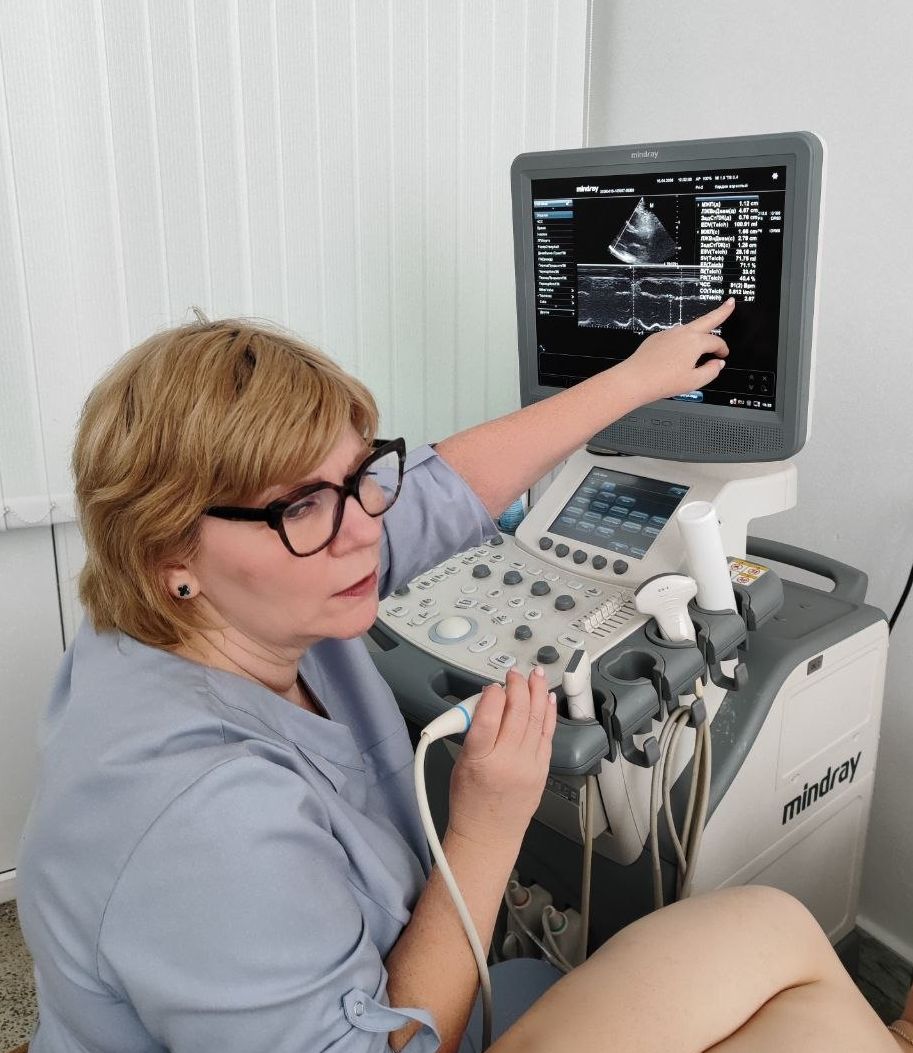

На кафедре лучевой диагностики с курсом ФПКиП дублёром заведующего кафедрой к.м.н., доцента Натальи Борисовны Кривелевич выступил студент пятого курса МДФ Кирилл Богомья. Занятие прошло в современном интерактивном формате. В теоретической части студенты не просто слушали лекцию, а активно работали с презентацией, разбирая сложные темы лучевой диагностики. Кульминацией теории стала интерпретация рентгенограмм: будущие врачи учились «читать» снимки под руководством своего старшего коллеги.

Главный сюрприз ждал ребят во время практической части. Наталья Борисовна и Кирилл организовали для группы экскурсию в кабинет РКТ (рентгеновской компьютерной томографии), а затем переключили внимание на ультразвуковые методы исследования. Под чутким руководством студента-дублёра и Натальи Борисовны каждый участник занятия получил уникальную возможность попробовать себя в роли врача ультразвуковой диагностики. Ребята освоили базовые протоколы сканирования: щитовидной железы, слюнных желез, почек и печени.

Настоящим подарком для студентов стал мастер-класс по эхокардиографии от Натальи Борисовны Кривелевич, которая продемонстрировала тонкости исследования сердца.